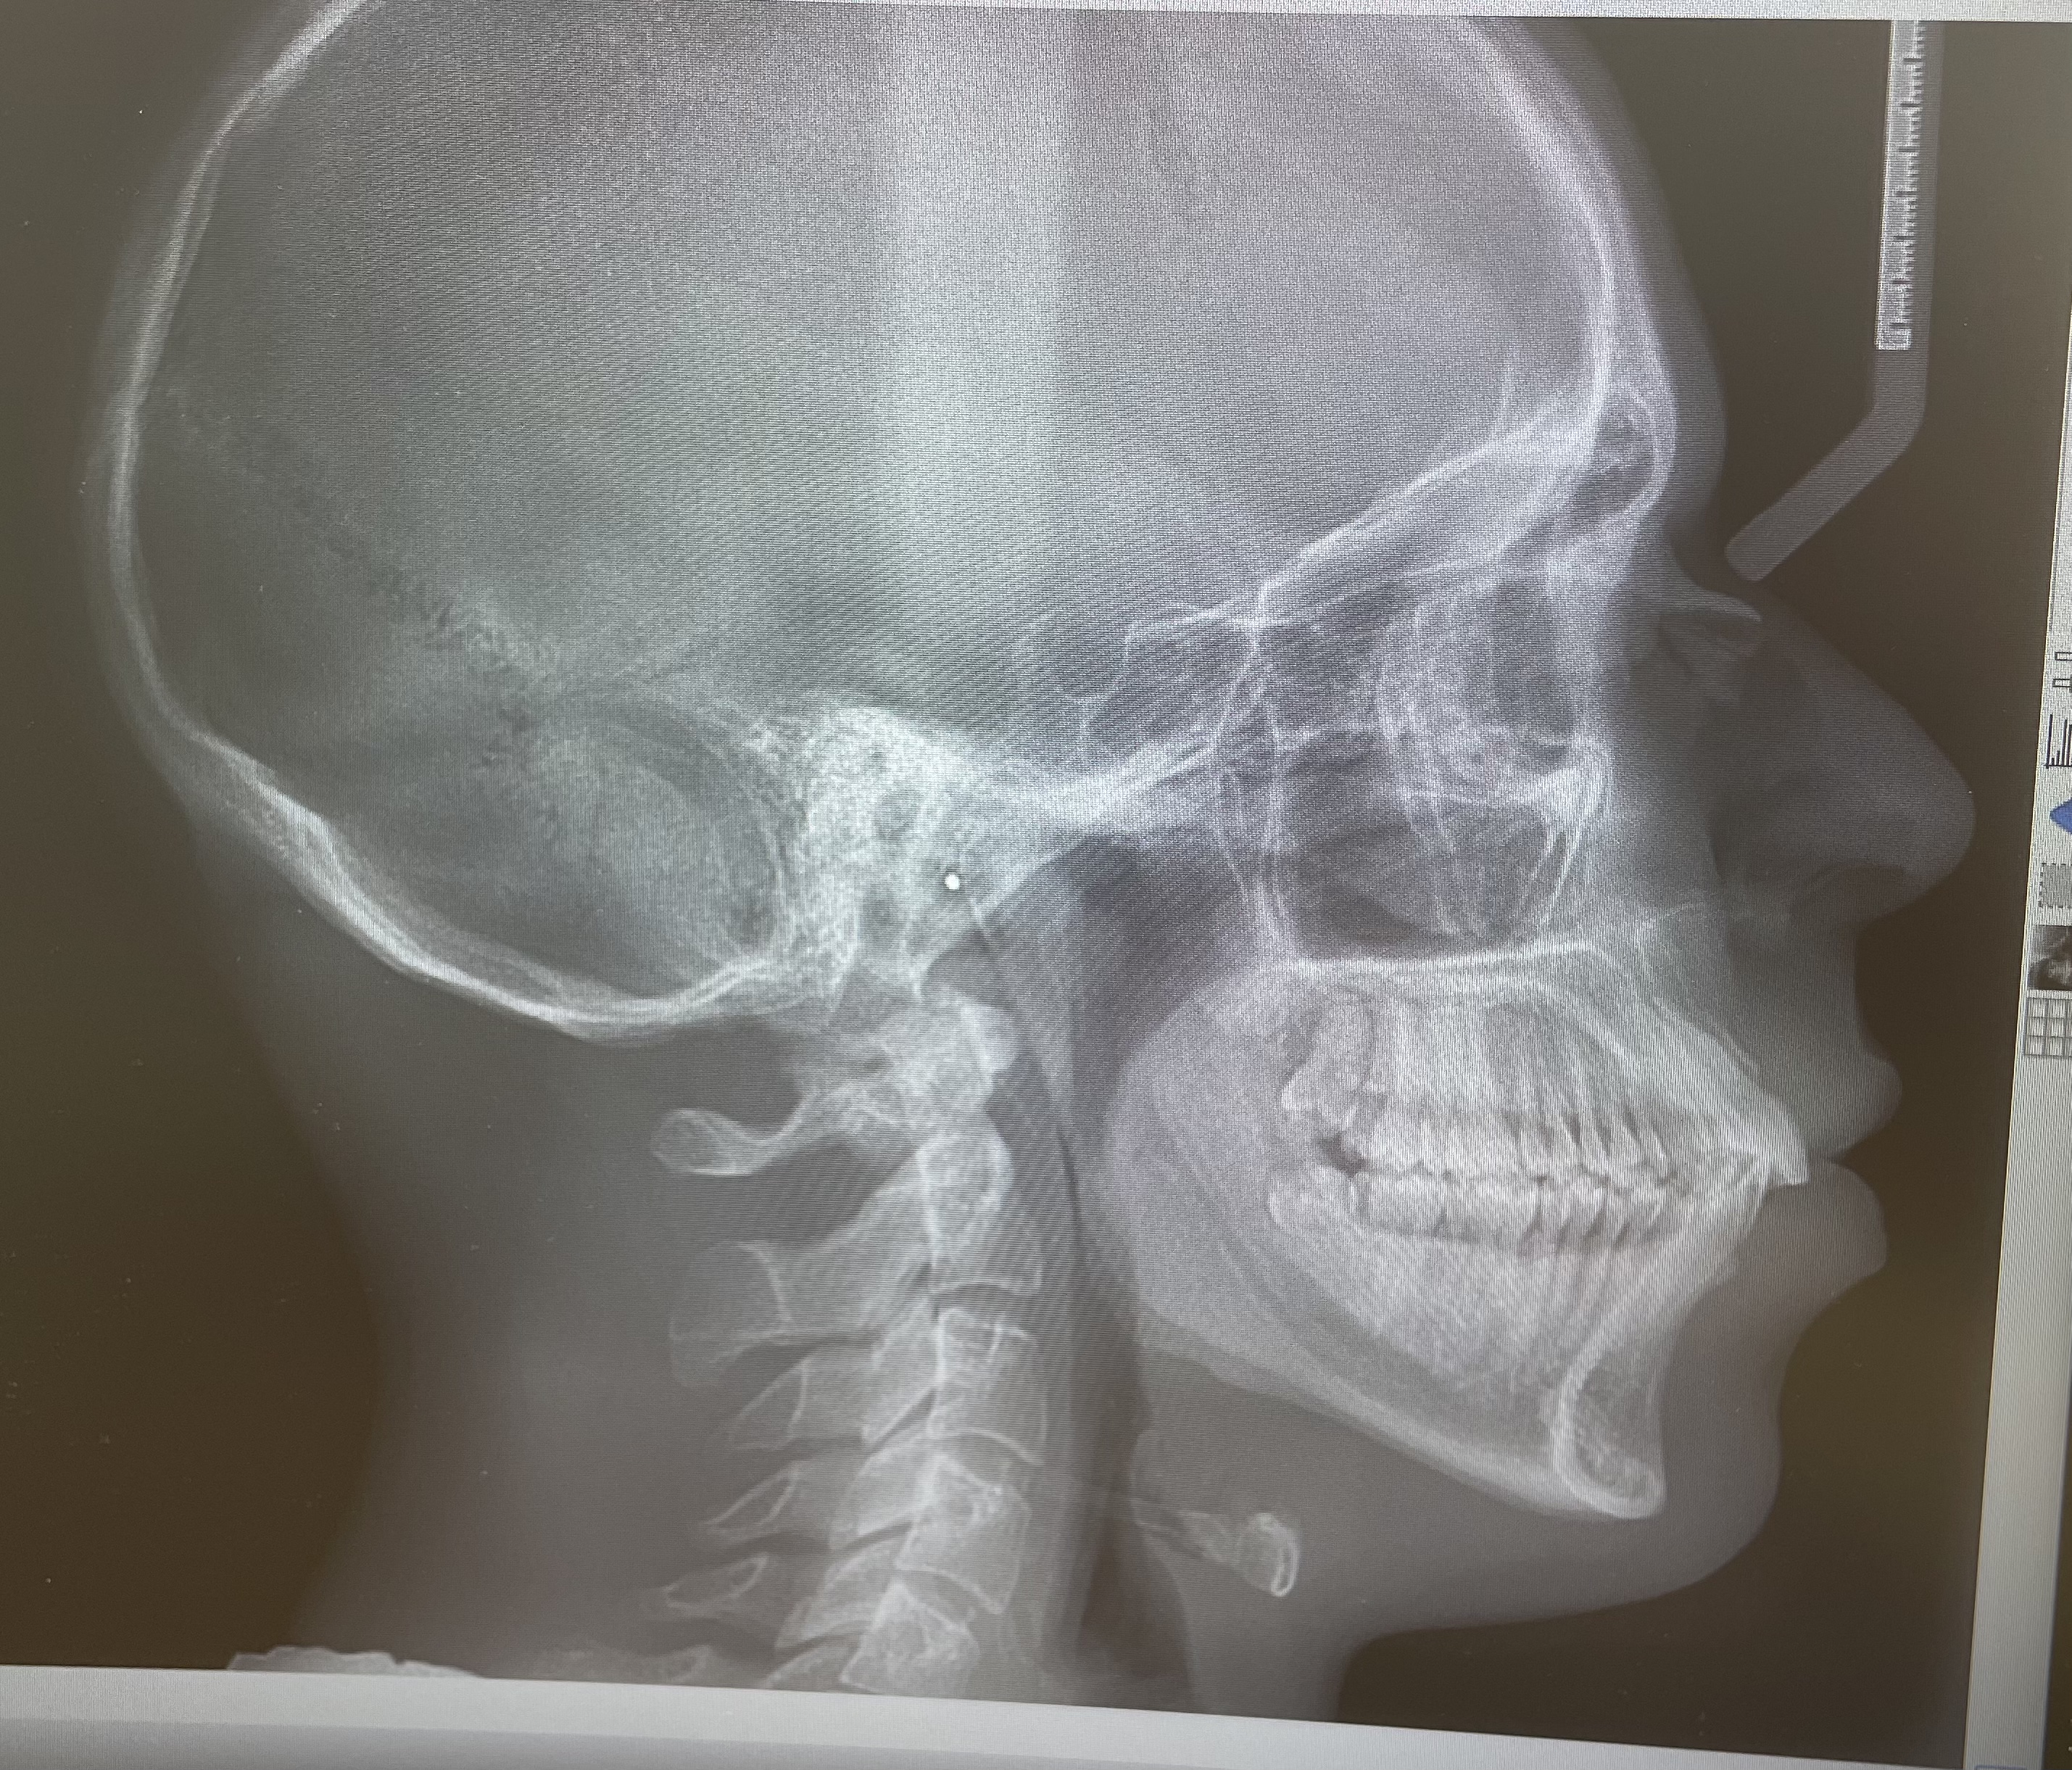

Just had a surgeon meeting, and he wants me to get a chin wing and braces to fix bimax.protrusion. He said my airways look normal, but i doubt it.

Would i benefit more from bimax+genio or even jaw implants. Im already mid-late20s